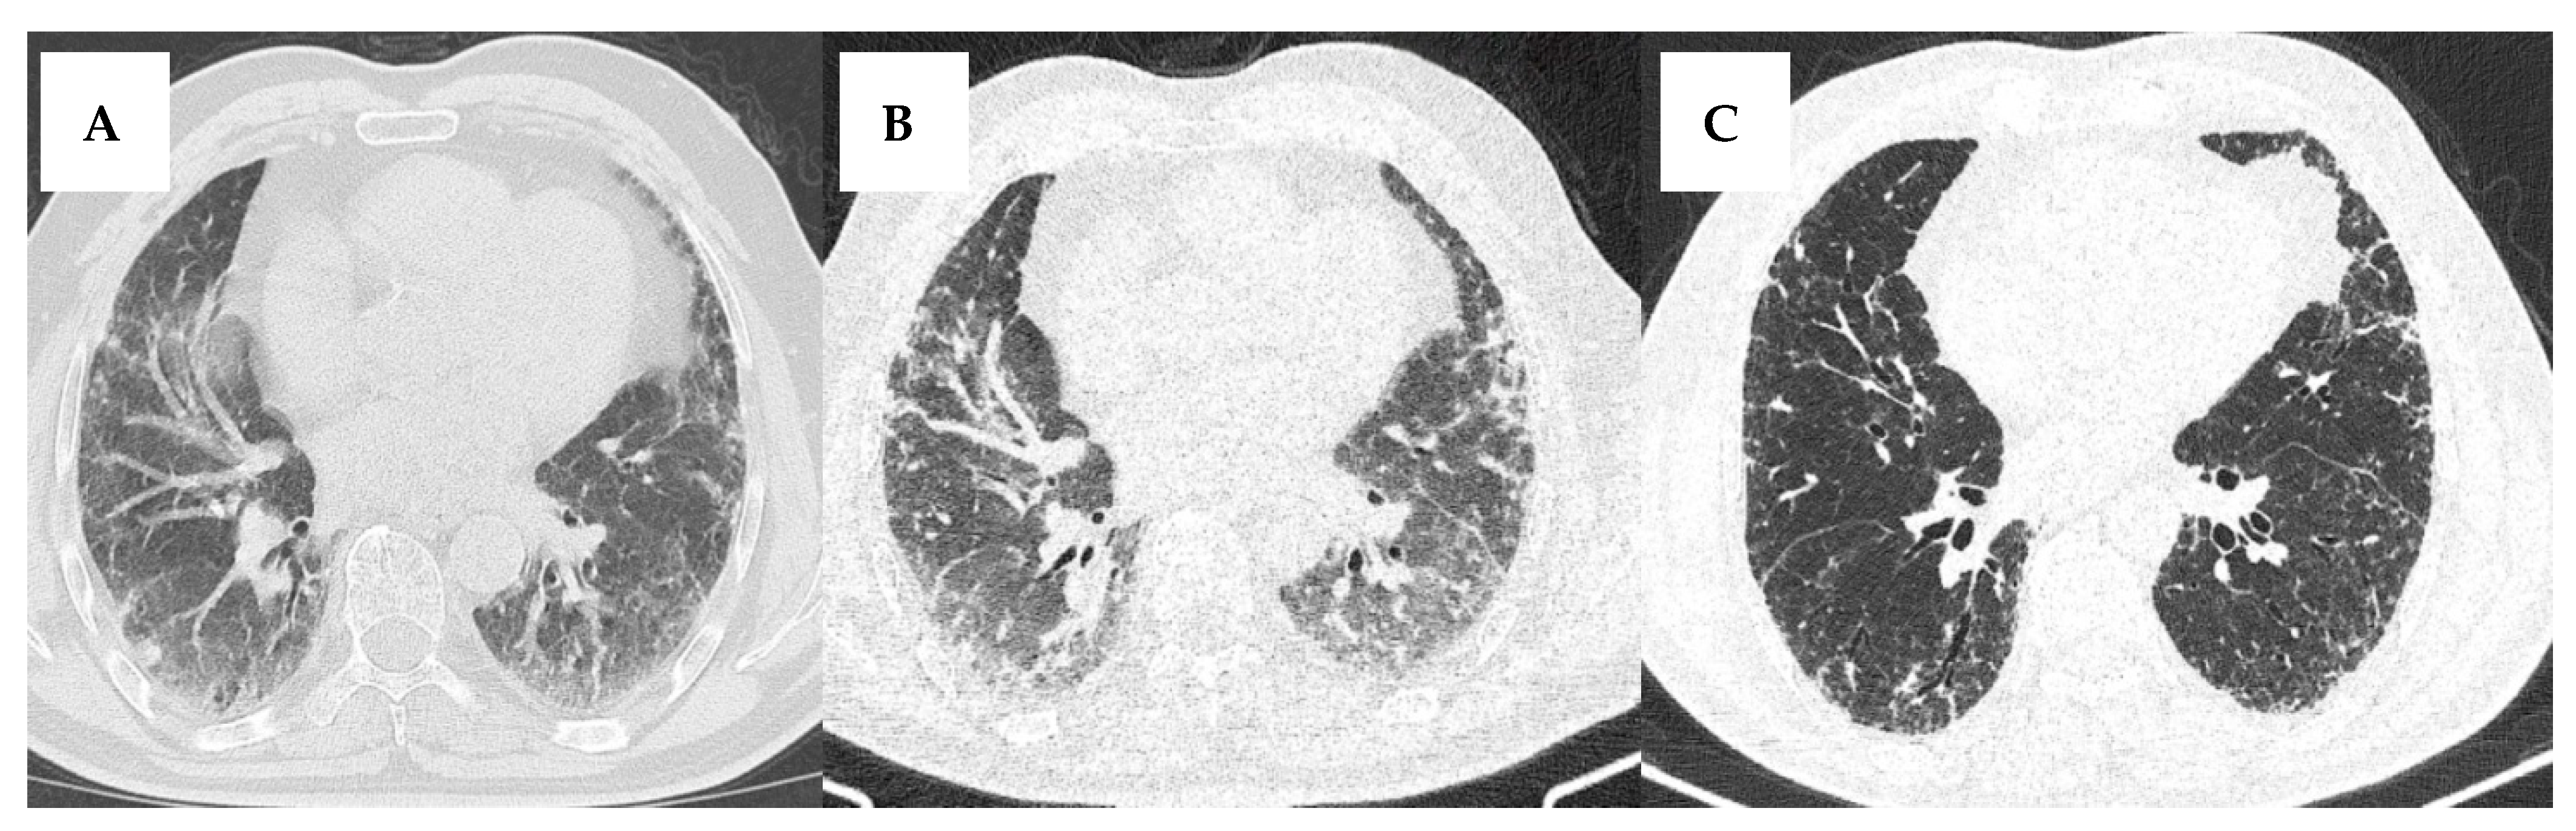

3.3.1. UIP Pattern

3.3.2. NSIP Pattern

3.3.3. OP Pattern

3.3.4. LIP Pattern